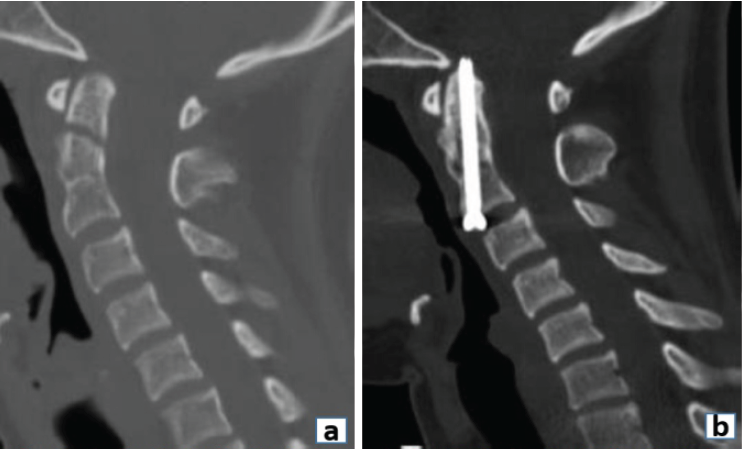

Anterior odontoid screw fixation also falls under the purview of spinal fixation. We aim for fracture union (fibrous or bony) with an anterior odontoid screw to reduce the risk of non-union and persistent neck pain in a stable spine setting (Fig. 3).

Figure 3: (a) Pre-operative Sagittal computed tomography (CT) image demonstrating a type II Odontoid fracture. (b) 6-month post-operative sagittal CT scan image demonstrating fixation with anterior odontoid screw.